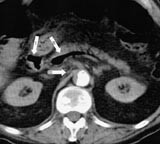

Ved ankomst i sykehuset var han kaldsvettende, forvirret og klaget over smerter i venstre bein. Han hadde ikke buksmerter. Han hadde puls 190/min, uregelmessig, systolisk blodtrykk 210 mm Hg og normal kroppstemperatur. Buken var lett utspilt, uten ømhet eller andre tegn på peritonitt. Venstre bein hadde nedsatt sirkulasjon. EKG viste raskt atrieflimmer. Pasienten var kritisk syk. Behandling av hans raske atrieflimmer med verapamil og metoprolol bedret ikke situasjonen. Blodprøver viste Hb 19,0 g/100 ml (jf. 17,4 g/100 ml to måneder tidligere), leukocytter 21,7 × 10 9 /l, trombocytter 226 × 10 9 /l, CRP 138 mg/l, natrium 141 mmol/l, kalium 3,3 mmol/l, albumin 42,3 g/l, kreatinin 140 µ mol/l, bilirubin 25 µ mol/l, ASAT 262 U/l, ALAT 139 U/l, CK 227 U/l, amylase 139 U/l. CT abdomen viste en normalt kalibrert aorta med tromber i venstre a. iliaca og i a. mesenterica superior. Det forelå en fyllingsdefekt nær avgangen av truncus coeliacus, samt fravær av kontrastfylling i coeliacusgebetet. Forgrening av luft var synlig i leveren (fig 1), helt ut til leverkapselen (fig 2). Luft var også synlig i den ekstrahepatiske del av portvenen, samt i miltvenen og i mesenteriale vener (fig 3). Det forelå ingen utvidelse av magesekken, og heller ingen intramural luft. Vi mistenkte en vaskulær katastrofe i buken. På vei til operasjonsstuen mistet pasienten bevisstheten og døde.